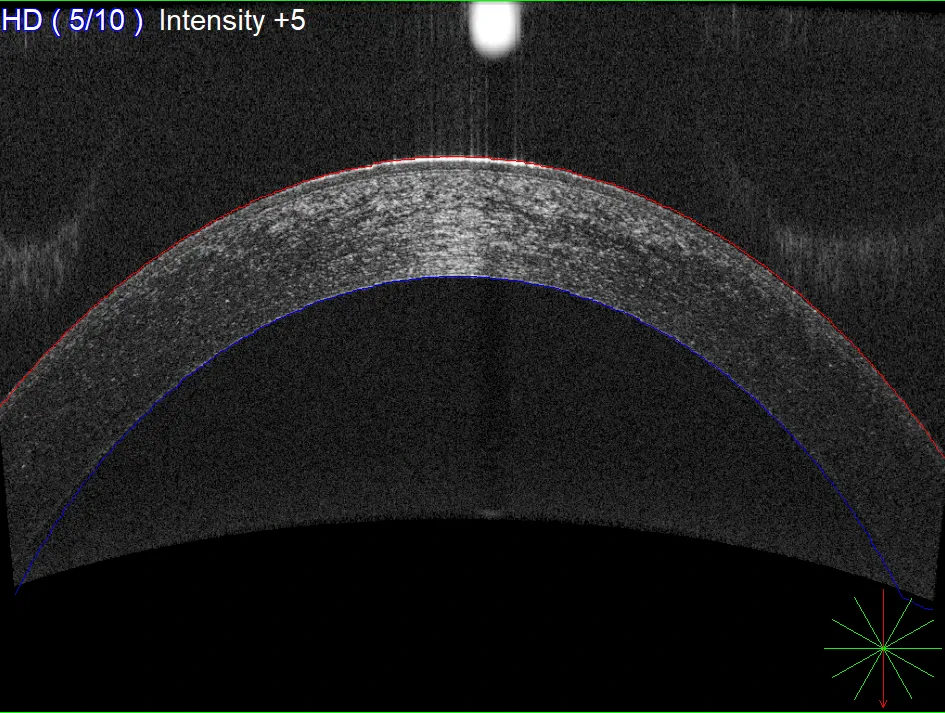

Pachymetry measures the thickness of the cornea, an important factor in evaluating eye health and accurately interpreting eye pressure readings. This test plays a key role in glaucoma assessment and helps identify corneal abnormalities, ensuring more precise diagnosis and safer long-term management of eye conditions.

Pachymetry scan